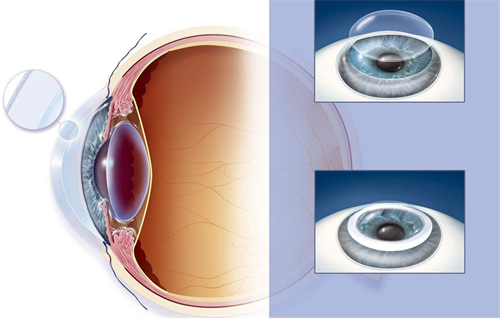

板层角膜移植:2万元起/单眼

适用人群:角膜浅层病变(如瘢痕、营养不良)

技术亮点:保留健康内皮层,排斥率≤5%,1个月即可拆线

穿透性角膜移植:4.5万元起/单眼

适用人群:全层混浊或穿孔(如化学伤、溃疡)

角膜内皮移植:3万元起/单眼

黑科技:3mm微切口植入,无需缝合,术后次日可视物,适合大泡性角膜病变